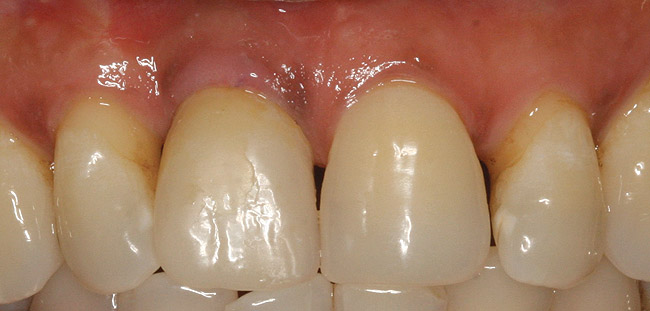

Following bone grafting and adaptation of the barrier membrane, the overlying flap was coronally positioned to achieve primary closure of the split alveolar ridge. After 4 months of healing, the site presented with ideal hard- and soft-tissue profiles (Figure 9). The implant was uncovered and a taller healing abutment was placed. A single crown was delivered (Figure 10), and the patient was restored to form and function.

Figure 9  Healing at 4 months.

Figure 9

Figure 10  Final restoration with porcelain-fused-to-metal (PFM) crown on tooth No. 8.

Figure 10